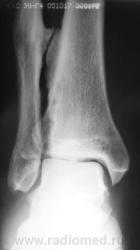

Пациент, в течение последних 2-х лет, жалуется на боли в нижней трети голени. Сегодня, хирургом, пациентка направлена на рентгенографию костей дистальной трети голени и голеностопного сустава. Что посоветуете уважаемые коллеги?

А что здесь советевать? Межберцовый неоартроз, вероятно, травматического генеза. Косой перелом н/л с признаками неполной консолидации. Попробуйте при производстве боковых снимков г/ст с-ва ( при травме) приподнимать пятку на 2-3 см.

Неоартроз между экзостозами? А что это за вздутие м/б кости на уровне неоартроза и пятнистость наружного кортикала? Следствие хронической воспалительной реакции?

Доброй ночи! Разволокнение коркового слоя, нечеткий очаг деструкции. Правда, нет секвестра. Если на увеличении не пригрезилось, то и линейный периостит. Вообще-то ответ был интуитивный, без логических обоснований. Ошиблась?

Какая-то непонятная структура костной ткани в области задней лодыжки.

Некоторая порозность, вероятно, нарушение трофики

В области внутренней лодыжки тоже пороз.